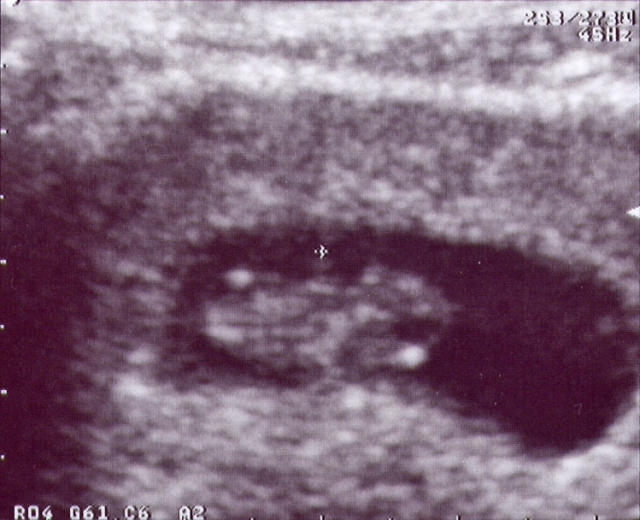

Here's my first picture. The technician is estimating that I am 8 weeks along at this point. I'm pretty small, but I'm growing fast.